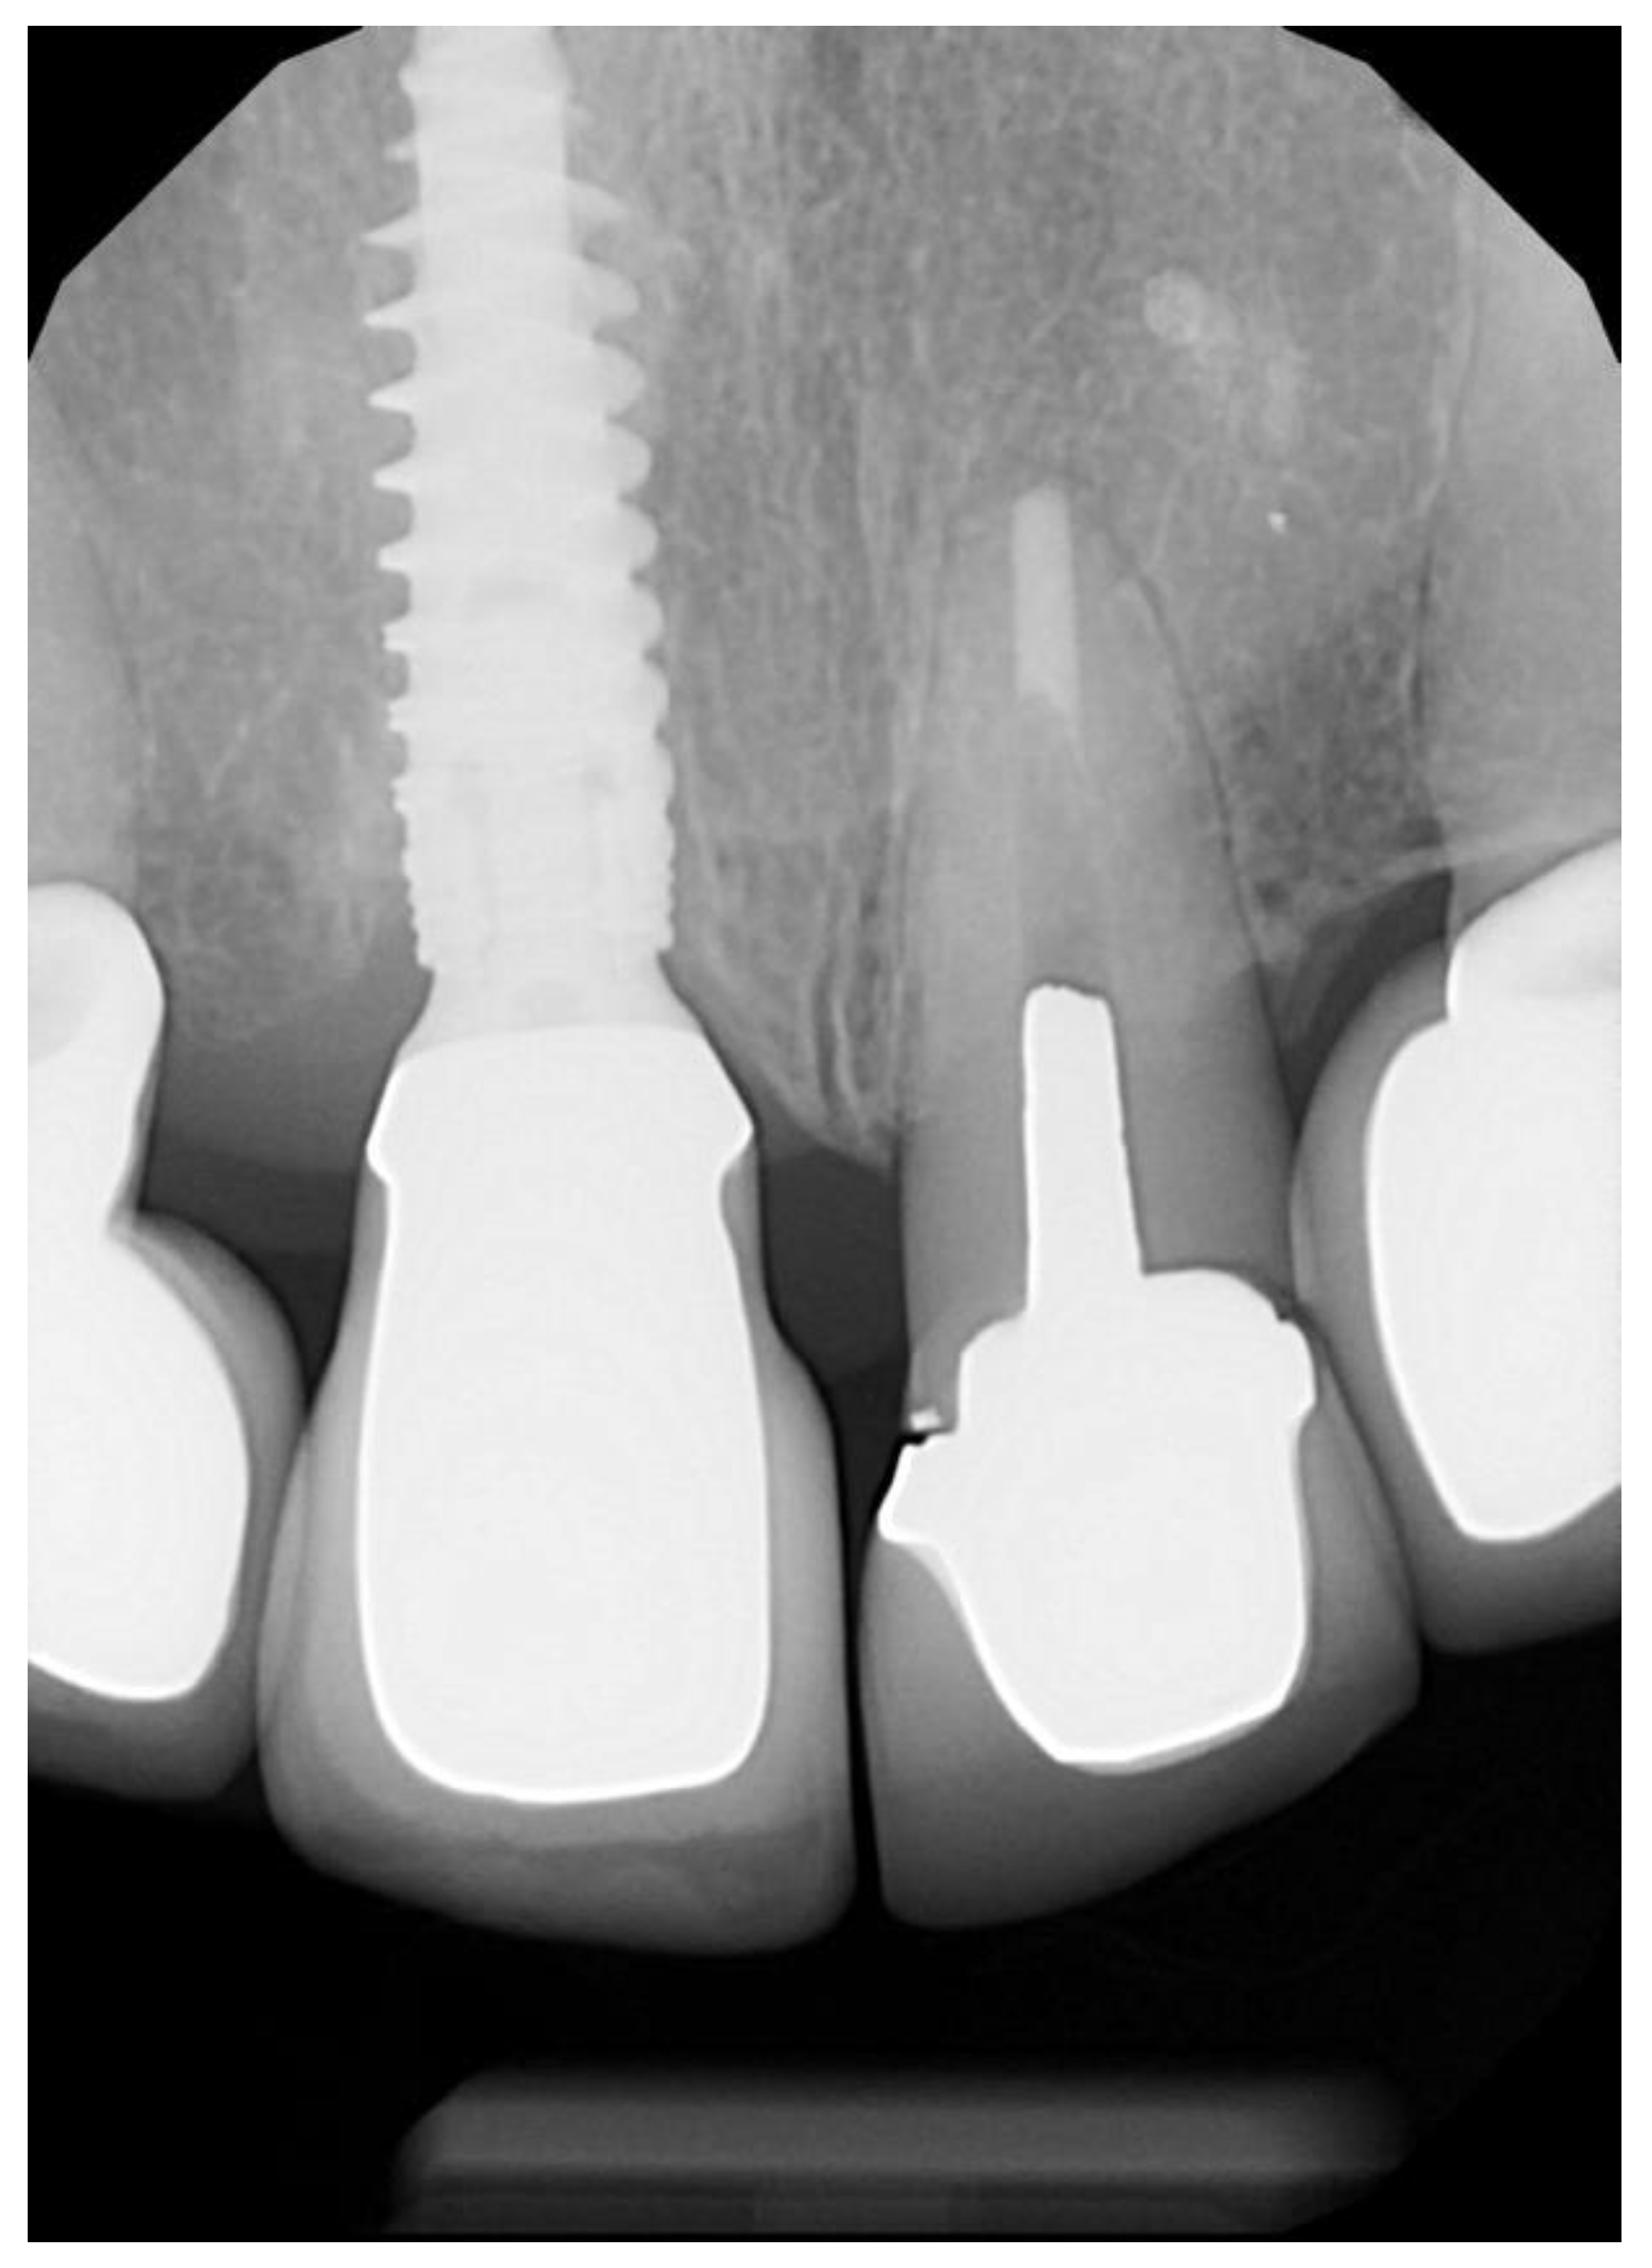

2.1. Surgical Technique